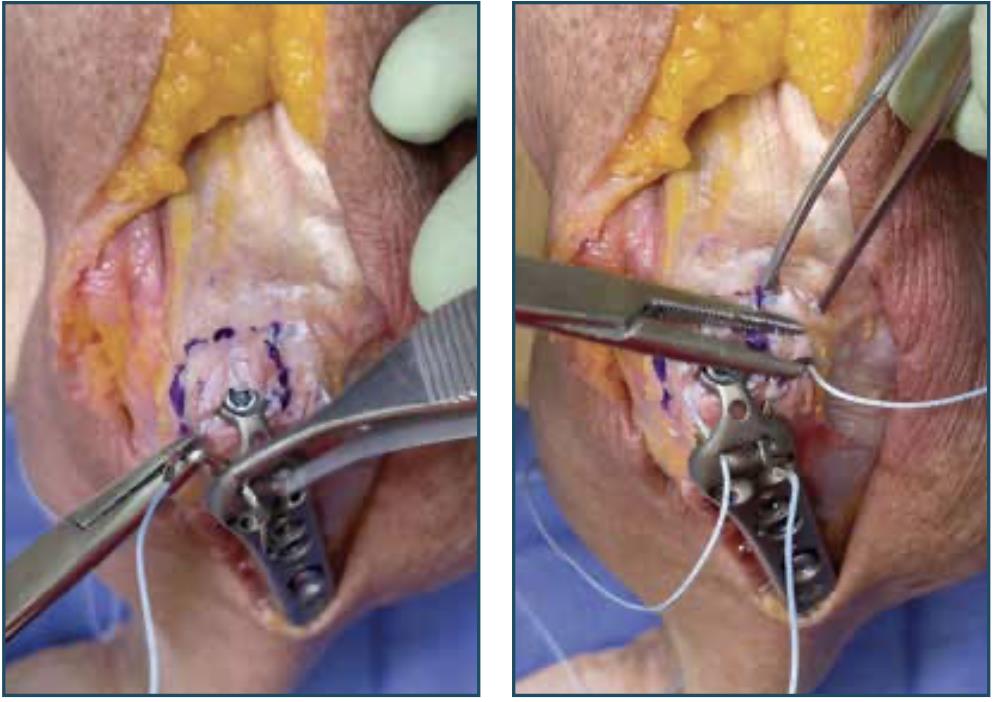

• Begin Passing Suture

• with the elbow in 90° flexion, mark a spot approximately 5mm distal to the home run tab

• Outline Suture Path

• draw an outline as shown to mark the suture path

• note: make sure the suture path goes through the medial head of the triceps tendon

• begin a non-locked running stitch along the lateral side

• pass the suture deep to capture as much of the underlying tissue as possible

• Continue Passing Suture

• continue passing the suture deep along the olecranon surface and the distal outline, incorporating Sharpey’s fibers

• continue the deep-running stitch medially

• Pass Suture Through Plate

• pass the suture through the medial suture hole of the plate, then pass the suture through the lateral suture hole of the plate

• Tie Sliding Knot

• tighten the suture to remove all slack

• pull suture limbs to confirm the suture slides within the tissue

• tie and tension a sliding knot on the lateral side

• Secure Construct

• secure the construct with six additional surgeon knots

• to avoid irritation of the soft tissue, ensure the knot stack is lateralized as much as possible